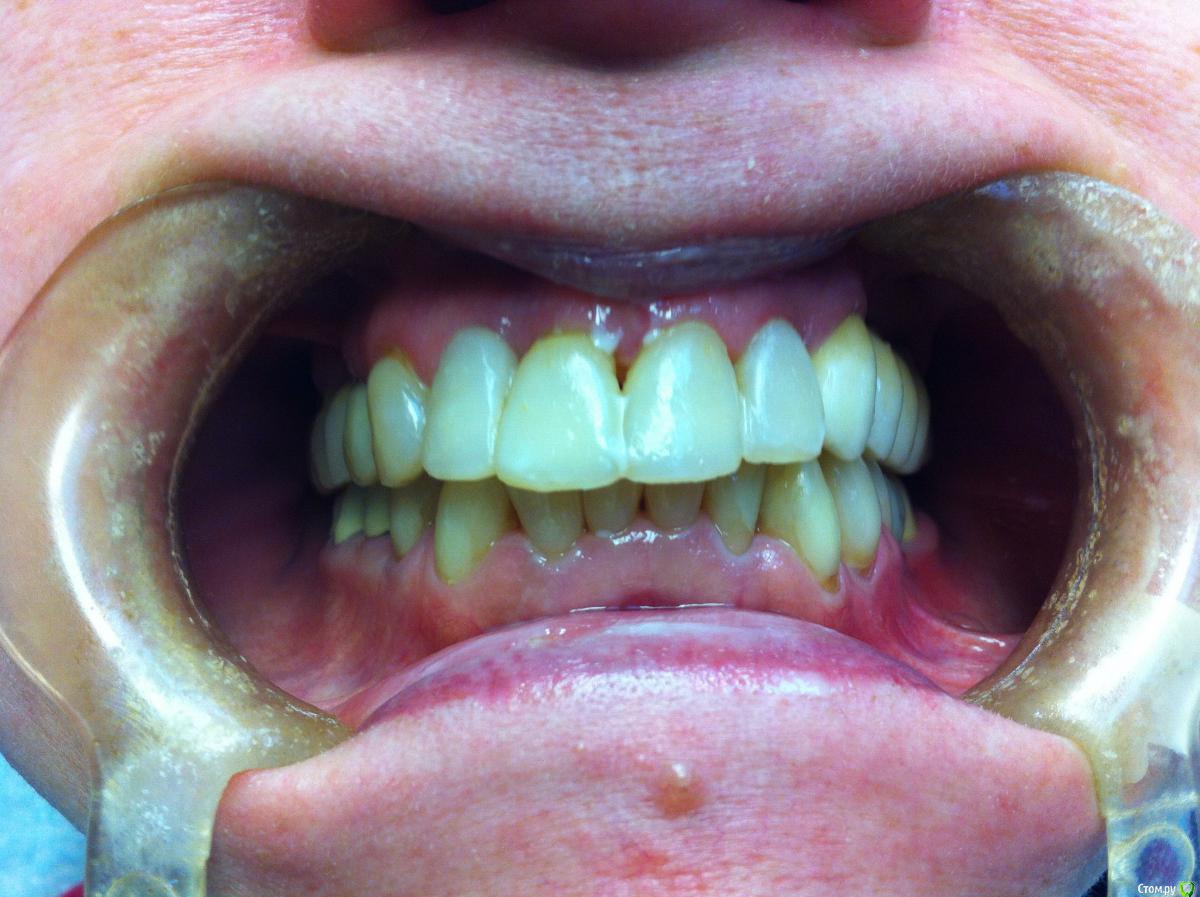

Айнур Фаязович Опубликовано 2 декабря, 2015 Поделиться Опубликовано 2 декабря, 2015 Пациентка обратилась с целью замены временной коронки на имплантате 36 на постоянную конструкцию. В ходе сбора анамнеза удалось выяснить, что 3 года назад у нее на 36 зубе произошла поломка винта внутри имплантата и, как следствие, появилась подвижность этой коронки. Ее доктору, у которого она протезировалась, удалось извлечь винт, но пришлось делать новую резьбу. Теперь она обратилась ко мне. Прилагаю фотографии полости рта, рентгеновские снимки до поломки винта, на момент обращения ( снимок с временной коронкой) и с трансфером для открытой ложки без винта (узкая платформа Астра). Дело в том, что у пациентки временная коронка на стандартном титановом абатменте ( платформа узкая 3,5-4,0) был зафиксирован с помощью винта от Dentium, при этом область шестигранника расширена изнутри ( чтобы проходил винт от Dentium) Но теперь возникают вопросы: 1)Как снять слепок с трансфером для узкой платформы, если родной винт не держится из-за изменения конфигурации резьбы, винт для широкой платформы и даже винт для Dentium слишком велики по размеру?2)Допустимо ли, по-вашему, менять конфигурацию постоянного абатмента в области шестигранника, расширяя его изнутри, чтобы проходил винт?3)Стоит ли проводить замену временной коронки на постоянную, если на рентгеновском снимке довольно серьезные повреждения в верхней части имплантата после изменения конфигурации резьбы. Уважаемые коллеги, если кто сталкивался с подобным, буду признателен за ваши варианты решений данной пробемы. За качество снимков прошу прощения, снимал на телефон. Ссылка на комментарий